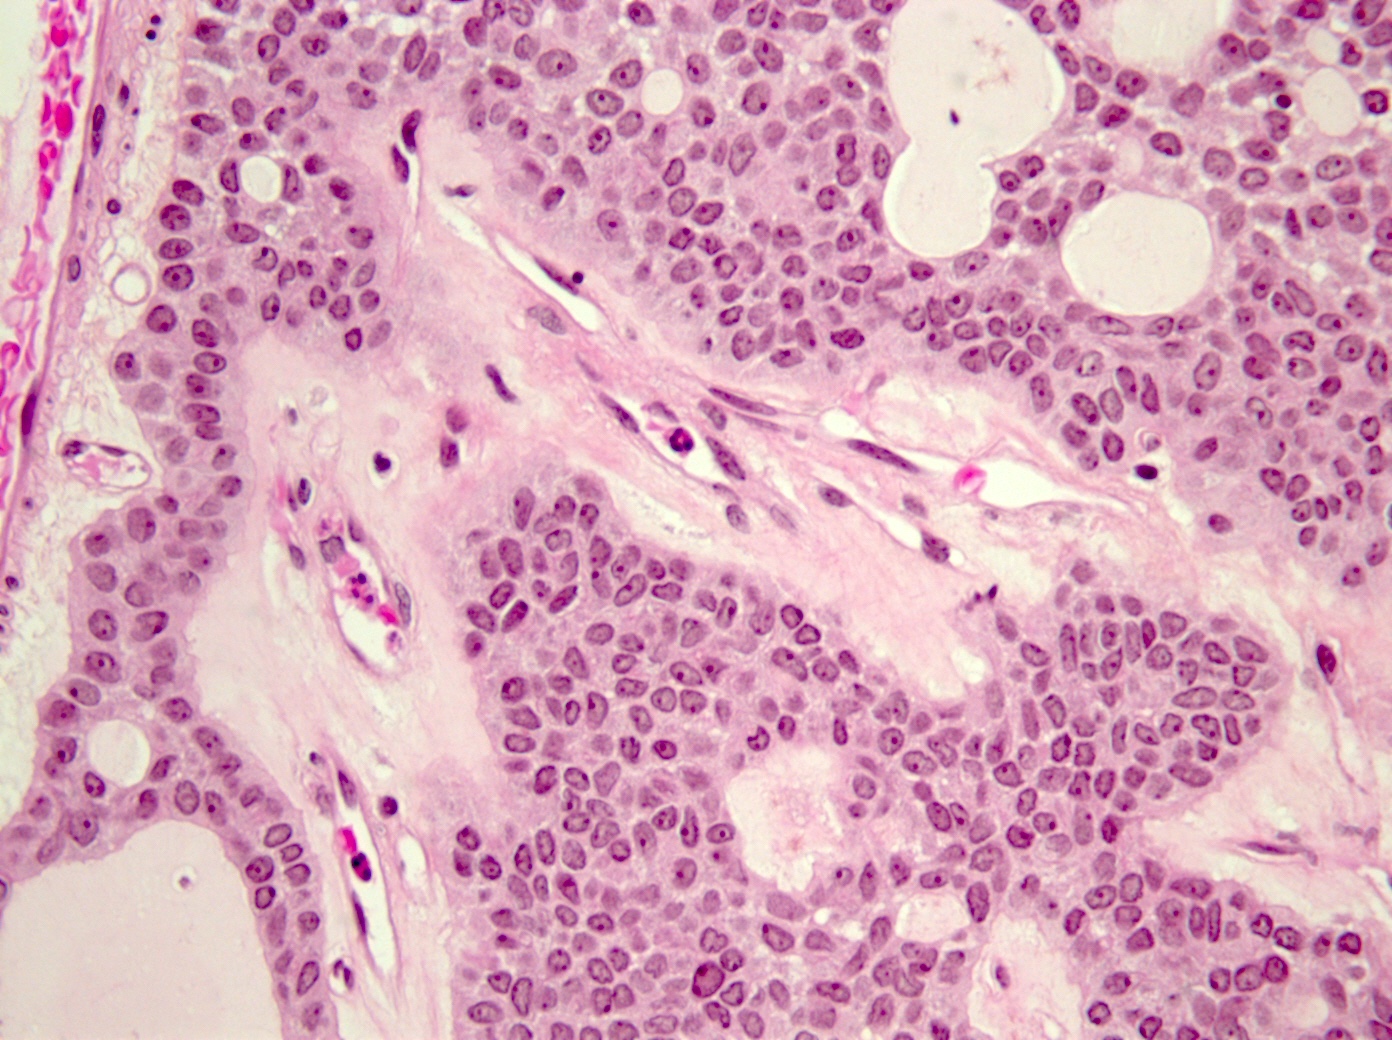

Microscopic (histologic) description

- Tumors may be single or multifocal

- Bilayered strands or ribbons or anastomosing cords or branching tubules

- Canalicular to cystic spaces between the cell strands; trabecular features

- Lack of an outer layer of myoepithelial cells

- Beading pattern, club ended cords

- May infiltrate capsule and show extracapsular tumor islands (including in the normal salivary gland / multiple tumors)

- Often cystic change

- Tumoral columnar or cuboidal cells, foci of basaloid cells

- Amphophil to eosinophilic cytoplasm, apocrine / oncocytic

- Round to elliptical, uniform nuclei, focally nucleoli, basophilic chromatin, rare to absent mitoses

- Mucous / mucinous metaplasia (Head Neck Pathol 2015;9:181)

- Pigmented cells

- Lacks or has exceptional necrosis (Head Neck Pathol 2015;9:181)

- Microliths, tyrosine crystals, morules and squamous balls (intraluminal) (J Craniomaxillofac Surg 2017;45:1754, Head Neck Pathol 2015;9:181, Histopathology 1999;35:502)

- Well vascularized, loose stroma; possibly sclerotic; perivascular eosinophil cuffs

- Luminal or stromal histiocytes (foamy, lipofuscin, hemosiderin), luminal hemorrhage, degenerated / infarcted stroma (Head Neck Pathol 2015;9:181)

- Malignant transformation not reported; lack of atypical figures (Head Neck Pathol 2015;9:181)

Microscopic (histologic) images